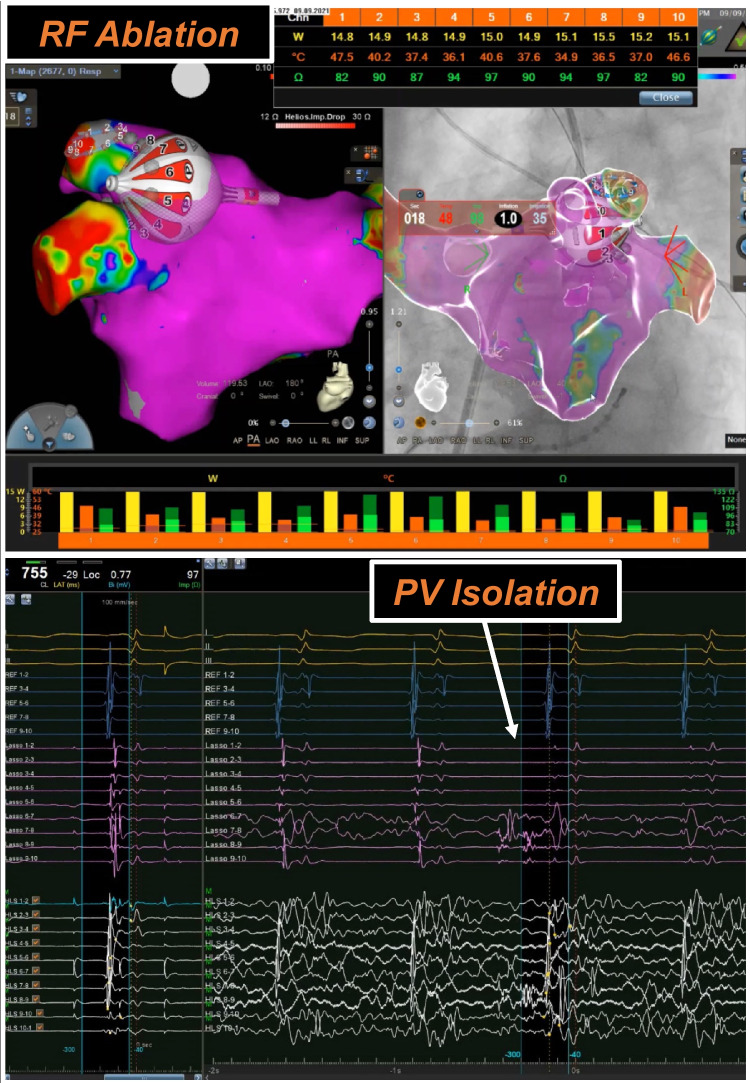

Background: A novel irrigated radiofrequency balloon (RFB) for pulmonary vein isolation (PVI) integrated into a 3D mapping platform was recently launched.

Results: A total of 99 patients were enrolled (43/99 (43.4%) women, median age 67 years (interquartile range [IQR] 59-74), 43/99 (43.4%) persistent AF (Pers-AF), median left ventricular ejection fraction (LVEF) 60% (IQR 62-55)). Eighty-eight patients completed the follow-up. Acute PVI was achieved in 383/383 (100%) PV. Single-shot PVI was achieved in 211/383 (55.1%) PVs. Primary adverse events occurred in 3% of patients (1 postprocedural pharyngeal bleeding, 1 myocardial infarction, 1 non-cardiovascular death); no pericardial effusion, stroke, or phrenic nerve paralysis was observed. Median ablation and procedure times were 23 (IQR 18-32) and 67 (IQR 57-85) min, respectively. Median dose area product was 761 (IQR 509-1534) mGycm2. AF-free survival after a median FU of 361 (IQR 261-375) days was 78.4% for paroxysmal AF (PAF) and 75.4% for Pers-AF (p value = 0.828). Early recurrence of atrial tachyarrhythmia at the 90-day visit was the only independent predictor for AF recurrence at 1 year upon multiple regression analysis (hazard ratio [HR] 3.198; 95% confidence interval [95% CI] 1.036-10.32, p value = 0.0433).

Conclusion: RFB-based PVI is acutely successful, appears safe, and has comparable rhythm outcomes to other single-shot AF ablation tools. A recurrence of AF at 90 days predicts later AF recurrence.